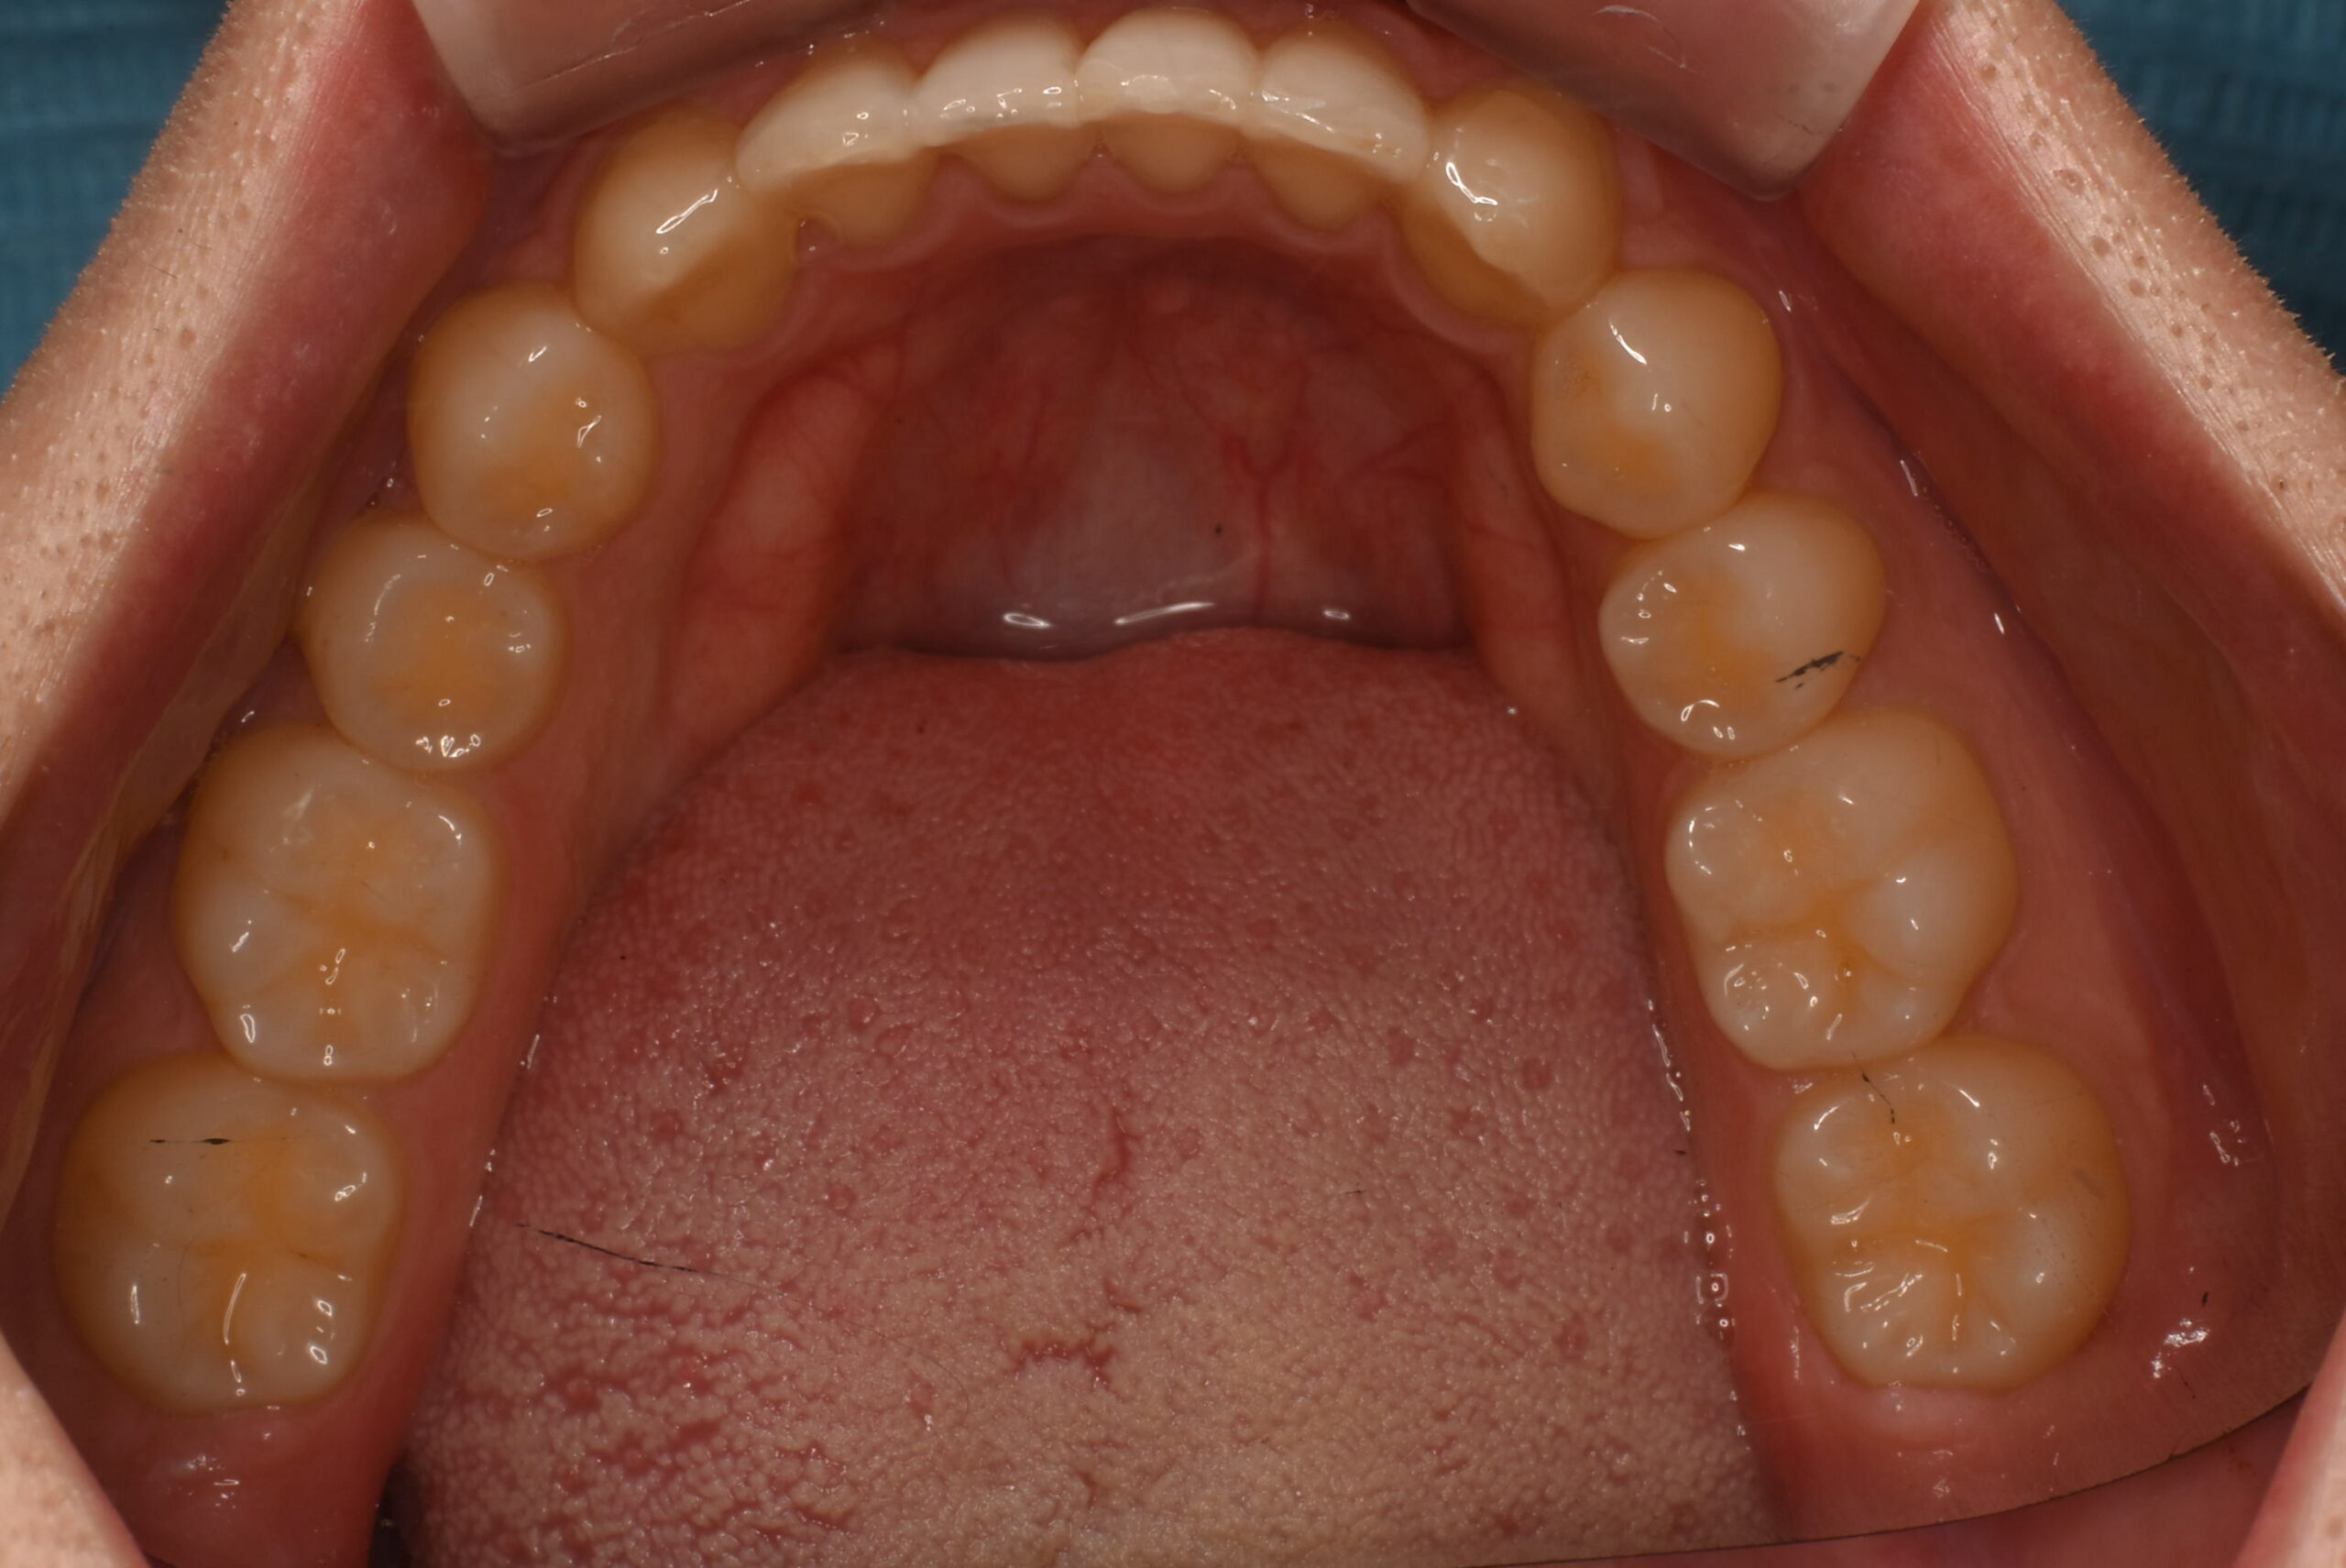

治療後_下顎咬合面

| 治療内容 | 患者様は、歯並びのガタつき(叢生)と、以前に顎関節症の治療経験があり、開口時に顎が「カクッ」と鳴る違和感を訴えて来院された。見た目の改善を希望され、目立ちにくいマウスピース型矯正装置による治療を希望された。 診査の結果、不揃いな歯列を認め、顎関節症の症状は安定していることを確認。インビザラインを用いて治療を開始し、必要最小限の歯間をわずかに削る処置を併用しながら歯列を整えた。 治療は40枚のアライナー終了後、患者様よりさらなる仕上がりを希望されたため、追加のアライナーを作成し治療を継続。結果として、患者様の希望通りの歯並びを獲得した。 |